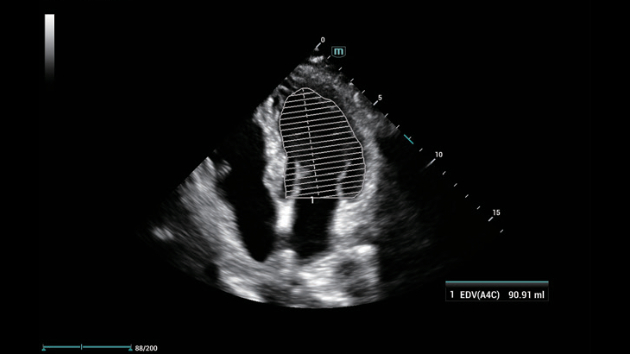

N?o importa se sua rotina ÃĐ em hospitais, clÃnicas ou se vocÊ estÃĄ aprimorando habilidades em Imagem Geral, SaÚde da Mulher ou na ÃĄrea Cardiovascular; vocÊ encontrarÃĄ ferramentas altamente poderosas disponÃveis para manter-se na vanguarda.

Solu??es abrangentes de imagens com tecnologia ZST+

A plataforma ZST+ ÃĐ uma inova??o extraordinÃĄria, representando a evolu??o do ultrassom. Transformando as mÃĐtricas de ultrassom: da forma??o convencional do feixe ao processamento baseado em dados de canais. Supera a limita??o de compensa??o tradicional entre resolu??o espacial, resolu??o temporal e uniformidade de tecido, oferecendo qualidade de imagem excepcional para solu??es de imagem infinitas com melhorias inigualÃĄveis.